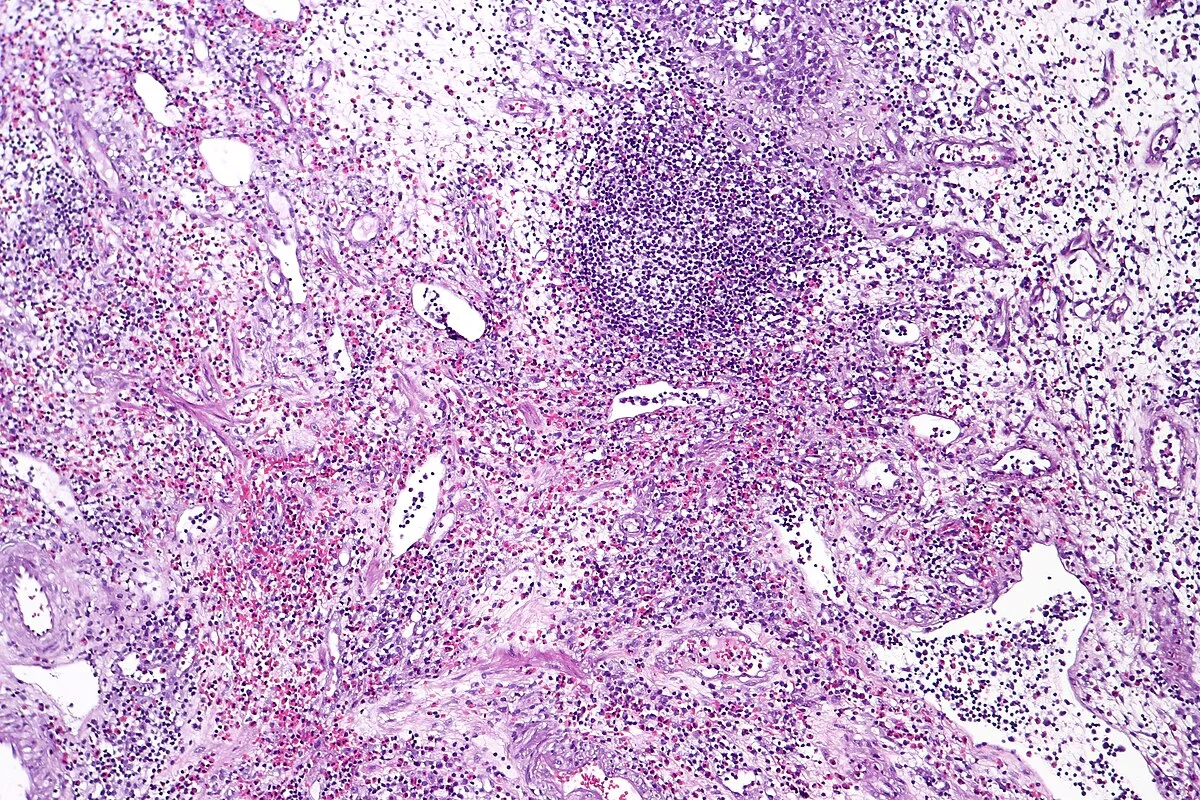

• Intravesical Immunotherapy (BCG): For high-risk tumors (high-grade or T1), simple removal isn’t enough. We use Bacillus Calmette-Guérin (BCG), a live, weakened bacterium related to tuberculosis. When placed in the bladder via a catheter, it triggers a massive immune response. The body’s immune cells attack the bacteria and, in the process, destroy the cancer cells. This is one of the most successful cancer immunotherapies in history.